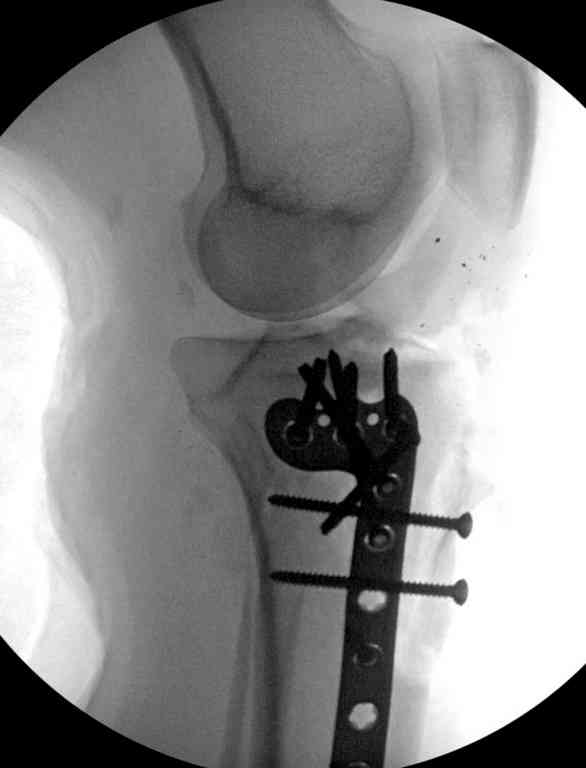

Поступила к нам пациентка 19 лет с диагнозом "Состояние после открытого многооскольчатого перелома дистального метаэпифиза правого бедра, проксимального метаэпифиза большеберцовой кости". Травма в июне 2010 года в Индии. ДТП.

Тамошние доктора выполнили ПХО с удалением фрагментов латерального мыщелка бедра. Наложен АВФ. По возвращению в Украину через 1,5 месяца АВФ демонтирован. И так как смещение фрагментов бедра не устранено, было принято решение после заживление ран от стержней выполнить МОС. Не сколько для четкой анатомической репозиции сколько для подготовки к установке эндопротеза в будущем. Что и было выполнено 10 августа. Интраоперационная картина следующая. Дефицит практически всего латерального мыщелка бедра. Была выполнена попытка закрепить то что осталось от мыщелка, но он развалился на фрагменты. ВЫполнен ситуационный синтез спицами. Дефект заполнили бикортикальным трансплантатом из крыла подвздошной кости, МОС страйкеровским фиксатором. В послеоперационном периоде к 10 дню начались боли, гипертермия. Повышение СОЭ, лейкоцитоз. Посев крови транзиторная бактериемия золотистого стаф. Взяли в операционную. Выполнили дренирование сустава и области п\о раны. Получили гематому фактически с гноем. Температура нормализовалась. Назначили ванкомицин по 1000 мг 2 раза в день.который принимает с 28 августа по сей день. Температура нормальная, СОЭ на убыль. Посевы отделяемого стафилококк 2 ст активности. Но отделяемое по дренажам продолжает идти в достаточном количестве. Взял посев, сеется стаф. 3 ст активноси. К ванкомицину, понятно, слабочувствителен. Что в этой ситуации посоветуете?

Коллеги фиксатор Numelock II

На вашем снимке из-за ротации трудно угадать положение пластины, и желательно сделать снимок с захватом верхнего участка бедра.

Одинокий кортикальный шуруп не удержит тибиальный бугор, сустав тибиал плато оставлен без репозиции и фиксации.